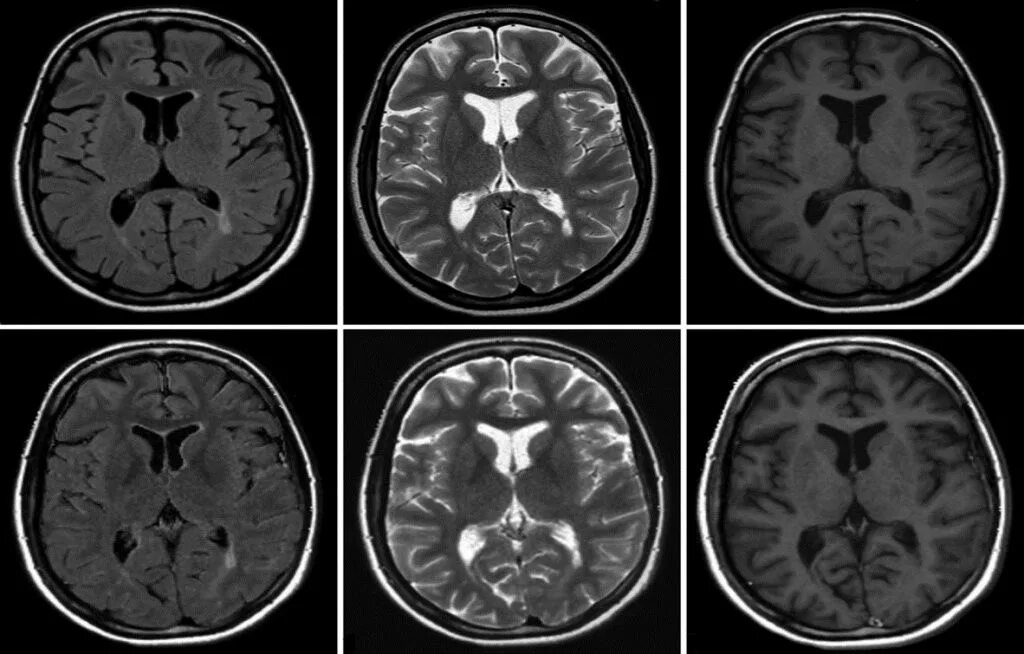

Какие виды кт